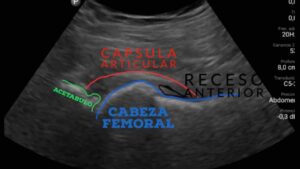

En algunos casos, puede ser necesario realizar una infiltración diagnóstica para asegurar el origen del dolor. Consiste en la inserción de una aguja en la zona afectada para inyectar un líquido que anestesia la zona. Si el dolor disminuye durante el procedimiento, indica que el origen del dolor está en la zona infiltrada.

La infiltración se puede realizar en quirófano o en el consultorio con ayuda de la ecografía. Si bien es una técnica muy útil para determinar el origen del dolor, la infiltración debe realizarse solo por médicos especialista en columna y cadera. En este vídeo lo explico en detalle: